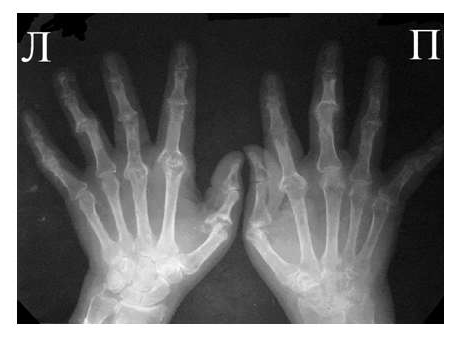

Для псориатического артрита, также поражающего мелкие суставы кистей, отличительным признаком от РА является отсутствие стадийности, поражение суставов, как правило, несимметрично, частые проявления артрита без околосуставного остеопороза, являющегося патогномоничным для РА. Изолированное поражение дистальных межфаланговых суставов кистей при отсутствии изменений в других мелких суставах кистей, осевое поражение 3-х суставов одного пальца.

Рис. 5 Множественный остеолиз и деструкции эпифизов костей с разнонаправленными деформациями суставов при псориатическом артрите.

При развернутой картине болезни деструкция концевых фаланг (акроостеолиз) и чашеобразная деформация проксимальной части фаланг пальцев кистей вместе с концевым сужением дистальных эпифизов симптом «карандаш в колпачке» (рис. 5), множественный остеолиз и деструкции эпифизов костей с разнонаправленными деформациями суставов (мутилирующий артрит).